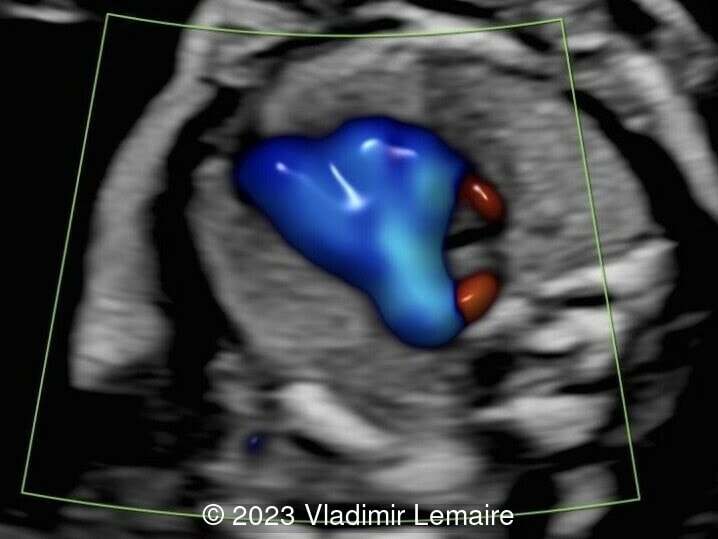

Aberrant right subclavian artery, seen in blue, in a fetus at 23 weeks of gestation.

Image 7 Aberrant right subclavian artery, seen in blue, in a fetus at 23 weeks of gestation.